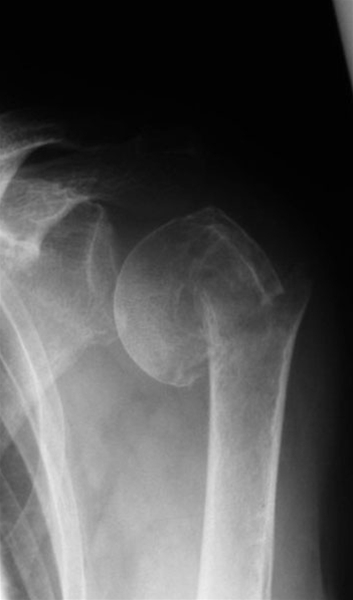

Proximal humerusfraktur, forskudt 4-part fraktur

4-part proksimal humerus fraktur. Der er forskydning af Tuberkulum Minor, Tuberkulum  Major og caput humeri.